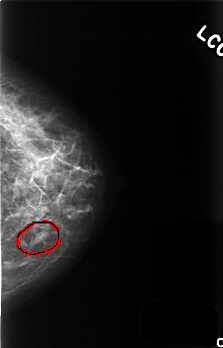

C_0507_1.LEFT_MLO

FILE: C_0507_1.LEFT_MLO.OVERLAY

TOTAL_ABNORMALITIES 1

ABNORMALITY 1

LESION_TYPE MASS SHAPE OVAL MARGINS CIRCUMSCRIBED

ASSESSMENT 3

SUBTLETY 5

PATHOLOGY BENIGN

TOTAL_OUTLINES 1

BOUNDARY